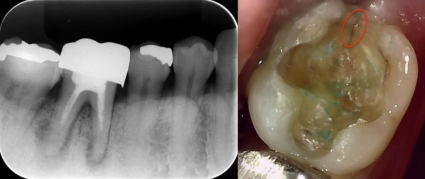

先日、右下奥歯が咬むと痛いという患者さんが来院しました。右下6番目と7番目の歯に痛みがあり、レントゲン写真から6番目は一度根っこの治療をしており、未だ根っこの先に病気があることが分かりました。6番目と7番目の歯には銀歯が入っていましたが、特に中で虫歯が広がっている様子は見られず、被せ物と土台の歯との間に隙間も見られなかったです。歯を叩いたときに響くこと、咬むと痛みがあるといったお口の中の症状とレントゲン写真における根っこの周りの黒く抜けている画像から6番目の歯を疑いましたが、7番目も咬むと痛みがあったことから、待機的診断を行い、1週間後に再度診査診断を行いました。1週間後にもう一度確認すると、歯を叩いたときは6番目と7番目、どちらの歯も響きましたが、7番目の歯の方が強く響き、咬んだときの痛みは6番目の歯では生じず、7番目の歯で生じたことから、7番目の歯が原因だと特定することができました。

今回のケースは銀歯を外してみると歯にクラックという亀裂があり、その隙間から細菌の感染が起こったことが原因であると考えられます。